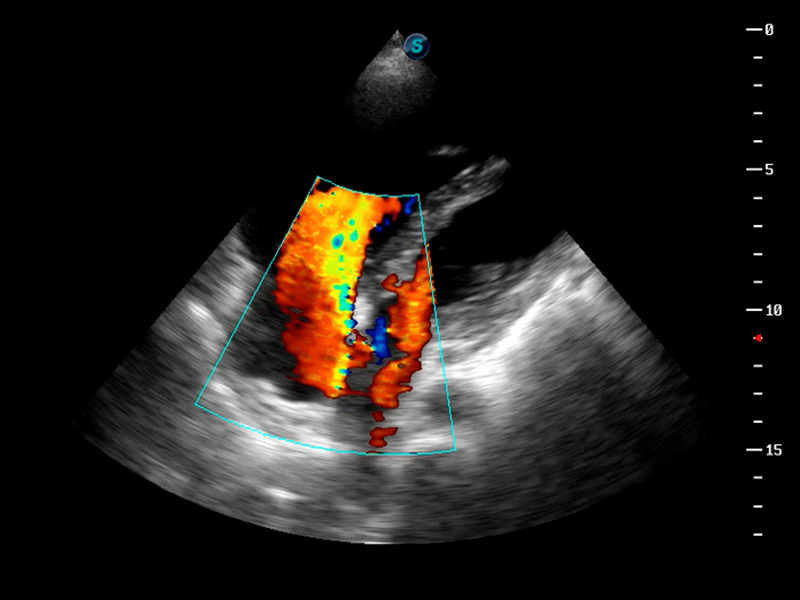

S9便携式彩色多普勒超声诊断仪是16877太阳集团研发的高端便携彩超设备,外观设计新颖、产品性能卓越。S9在便携超声领域采用了突破传统的触摸屏交互设计,并以先进的软件硬件技术和设计理念,为您带来清晰的图像质量、稳定的工作性能和便捷的操作体验。

TDI组织多普勒成像